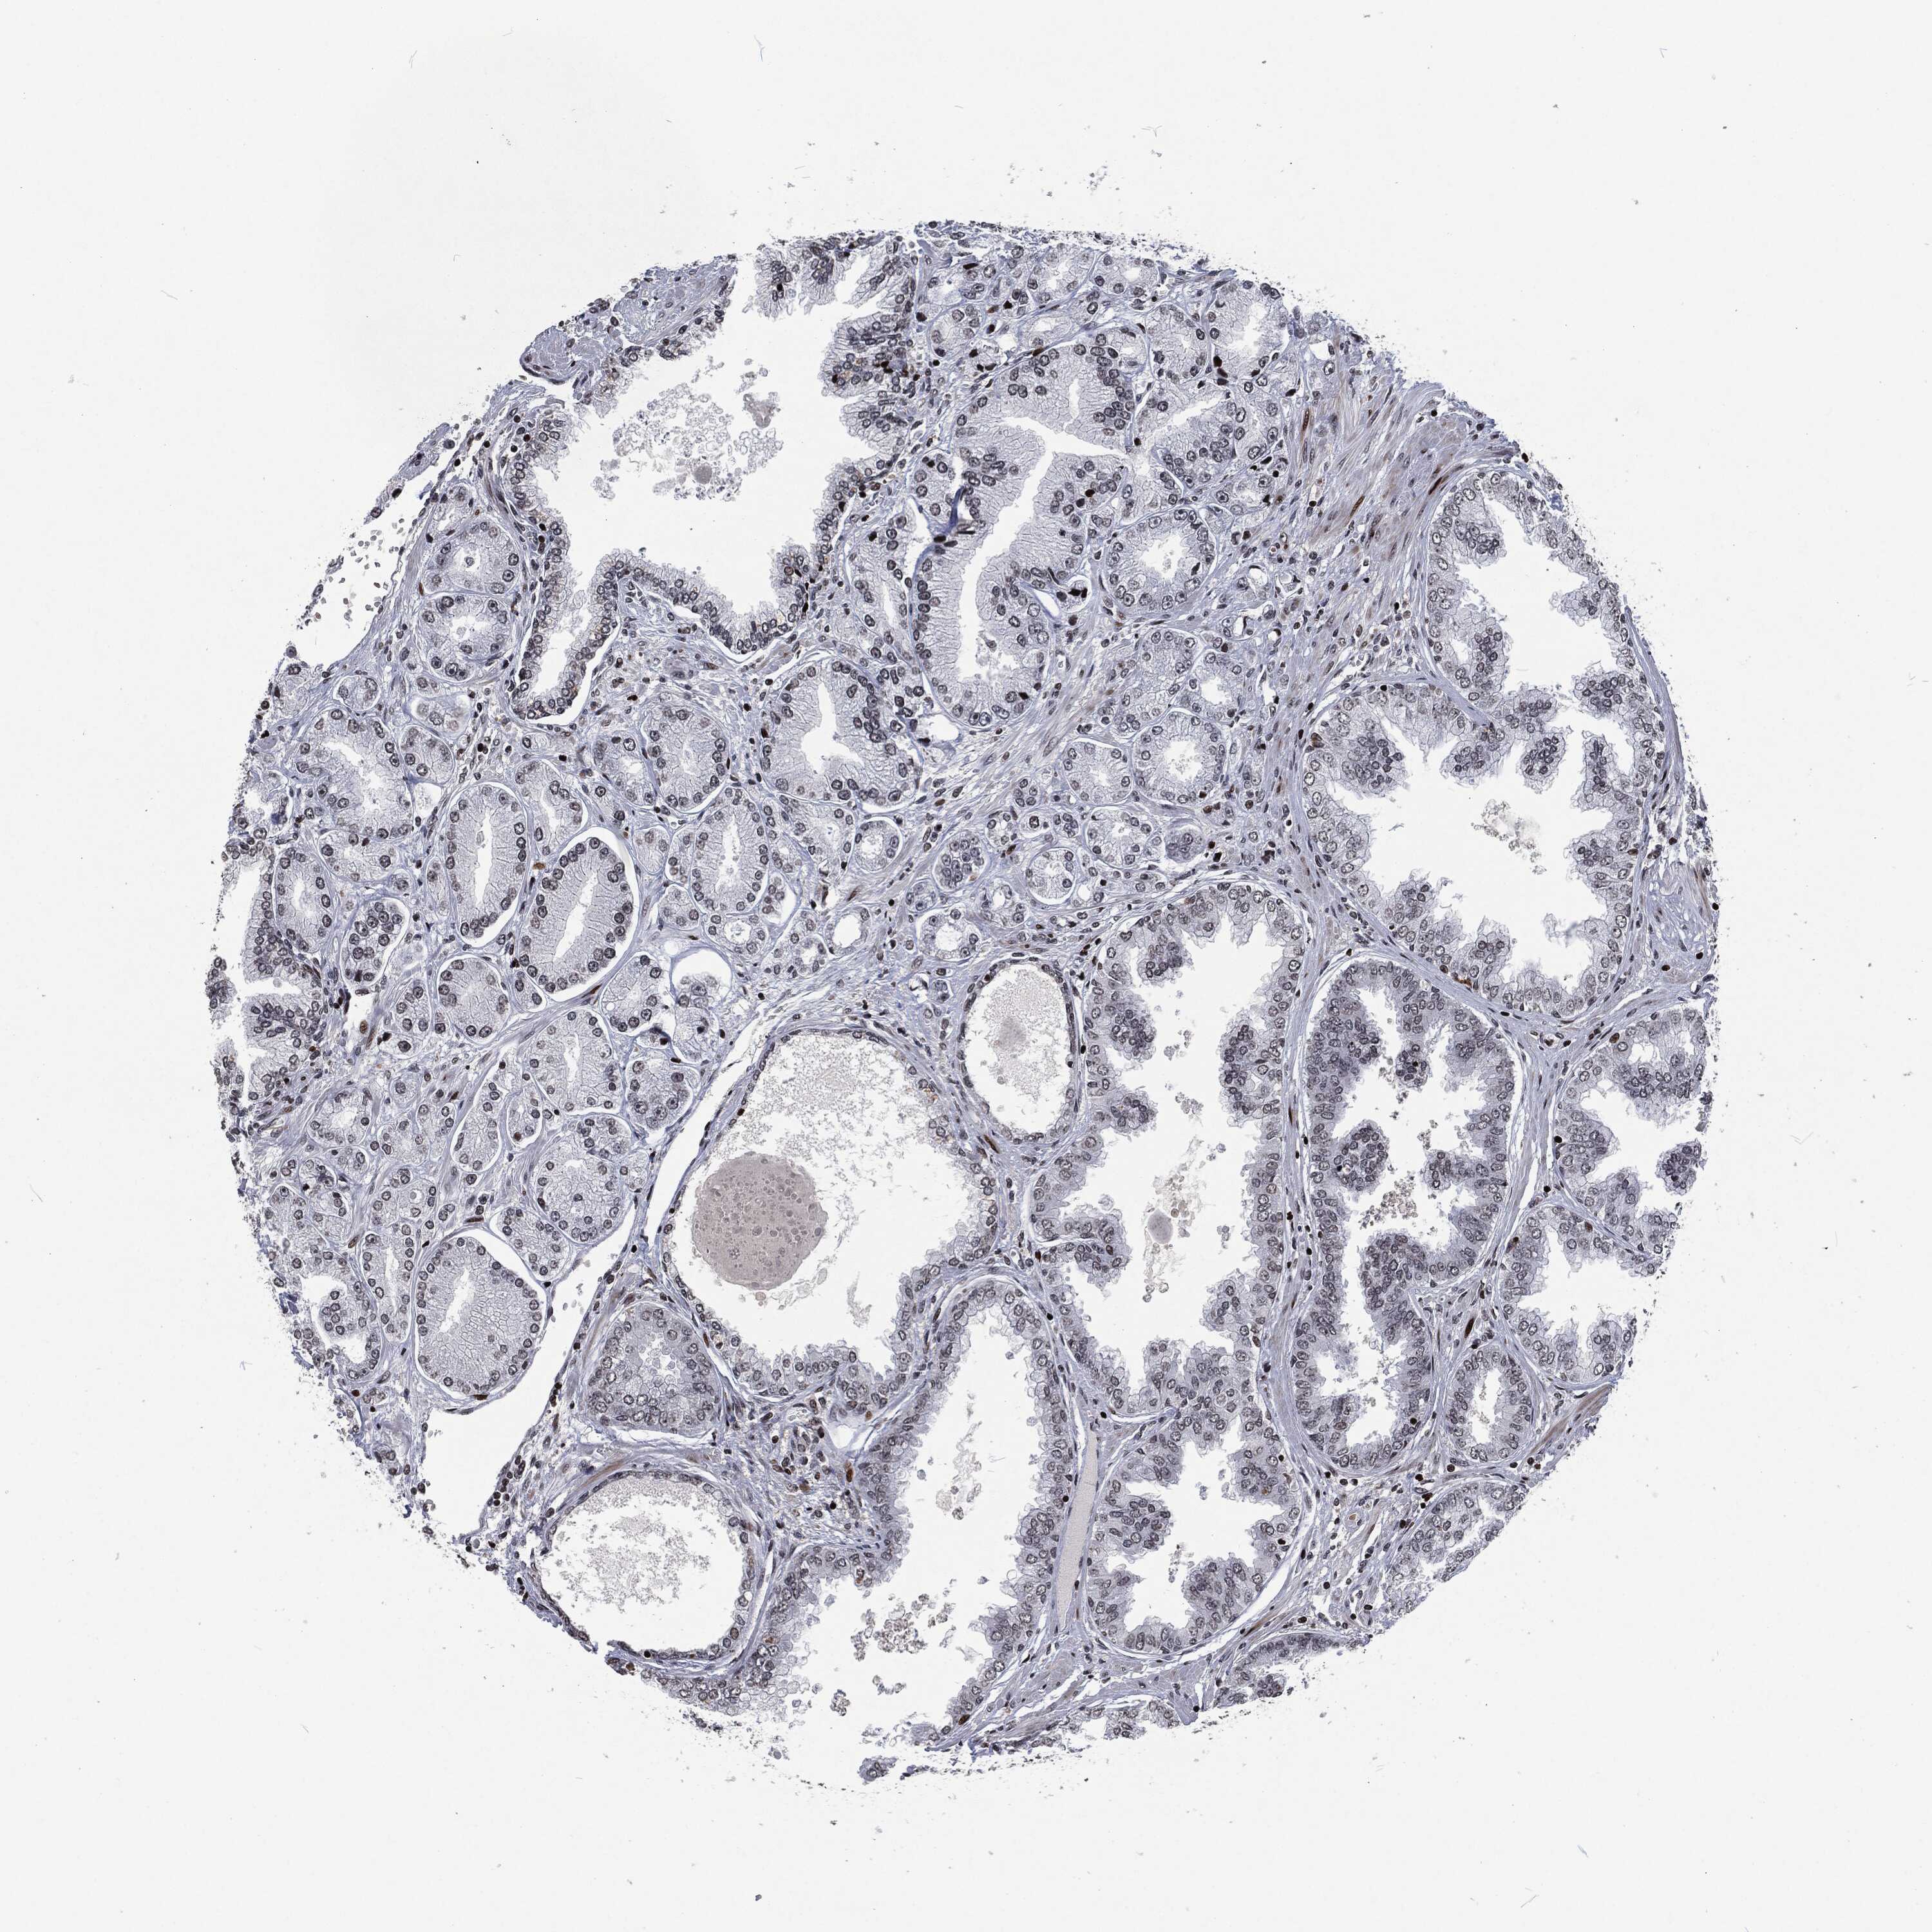

PROSTATE CANCER - Protein expressioni

A mouse-over function shows sample information and annotation data. Click on an image to view it in a full screen mode. Samples can be filtered based on level of antibody staining by selecting one or several of the following categories: high, medium, low and not detected. The assay and annotation is described here.

Note that samples used for immunohistochemistry by the Human Protein Atlas do not correspond to samples in the TCGA dataset.

Antibody stainingi

Antibody staining in the annotated cell types in the current human tissue is reported as not detected, low, medium, or high, based on conventional immunohistochemistry profiling in selected tissues. This score is based on the combination of the staining intensity and fraction of stained cells.

Each image is clickable and will lead to virtual microscopy that enables deeper exploration of all samples and also displays staining intensity scores, fraction scores and subcellular localization as well as patient and tissue information for each sample.

Adenocarcinoma, Medium grade

Adenocarcinoma, Low grade

Adenocarcinoma, High grade

Adenocarcinoma, NOS